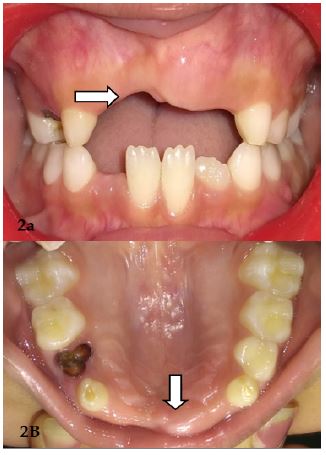

Extraorally, there were no significant findings (Figure 1). Intraorally, patient had mixed dentition with missing maxillary incisors but had slight elevation of left anterior alveolar ridge in the region of left maxillary central incisor (Figure 2a and 2b). Provisionally it was diagnosed as an odontome in maxillary anterior region.

Figure 2: (A) Showing the teeth in occlusion. (B) Showing maxillary arch.